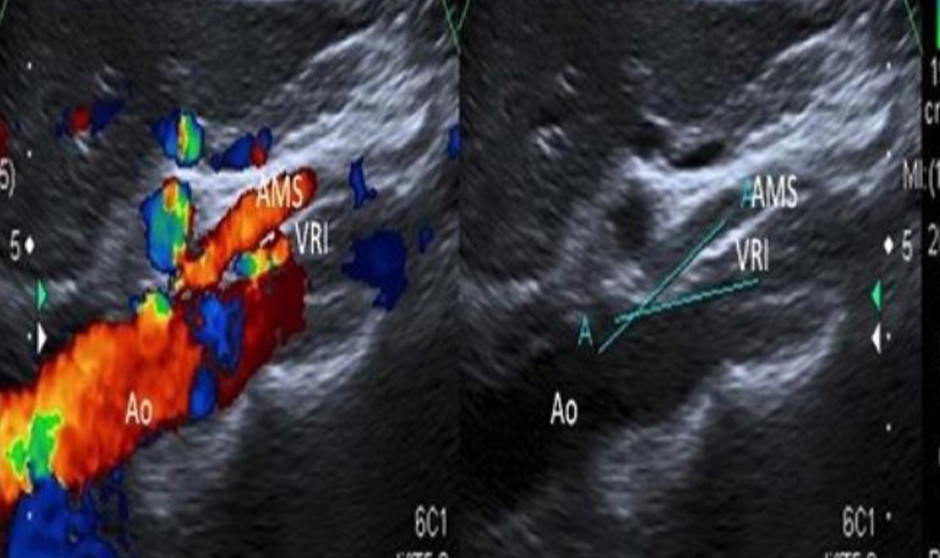

Una imagen de una ecografía Doppler.

El Doppler —especialmente el Doppler color— se emplea fundamentalmente con tres objetivos:

• Realizar procedimientos sobre estructuras vasculares.

• Planificar intervenciones evitando lesionar vasos sanguíneos.

• Controlar y tratar posibles complicaciones vasculares.

Una de las principales ventajas del Doppler es que permite visualizar las estructuras vasculares en tiempo real, identificarlas con precisión y, en procedimientos destinados a trombosar vasos, comprobar en directo la desaparición del flujo sanguíneo. "En intervenciones percutáneas —como drenajes, biopsias o ablaciones— el Doppler es clave para identificar vasos que podrían lesionarse inadvertidamente, como la arteria epigástrica en procedimientos abdominales. También permite detectar vasos en el entorno de una ablación, donde pueden actuar como puntos de fuga de calor, ayudando al especialista a modificar la técnica si es necesario", ha subrayado Del Cura.